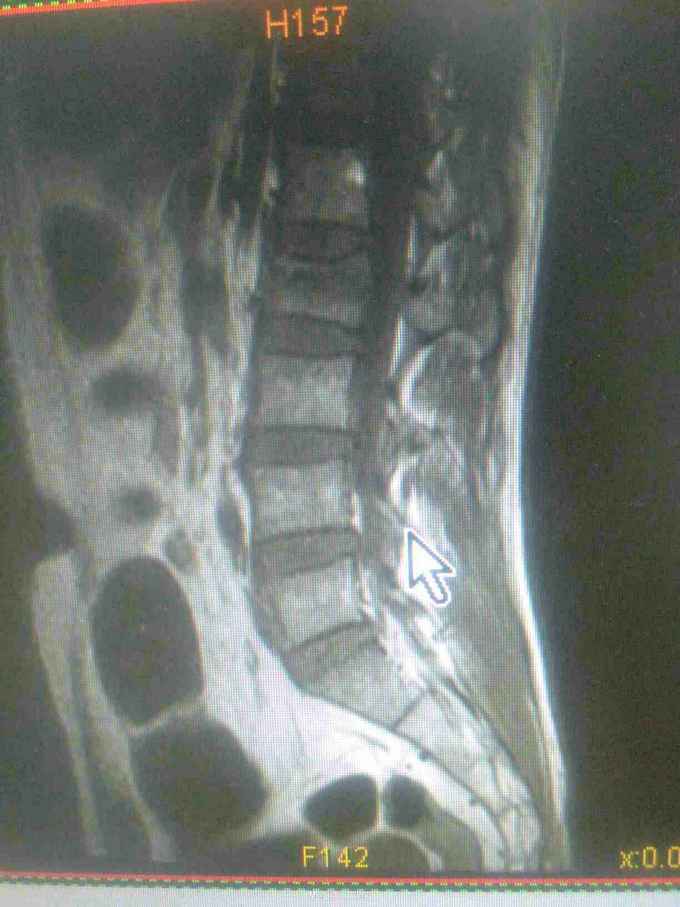

一例腰椎骨折行经皮椎弓根钉内固定术

查体:腰2椎体棘突压痛明显,双下肢肌力、肌张力正常,腱反射可引出,感觉正常,未引出病理反射。

诊断:腰2椎体压缩性骨折。手术:于插管全麻下行经皮椎弓根钉内固定术。

第一次做,请指教。钉子长了点,棒短了点,但没出。除此之外,还有哪些欠缺。